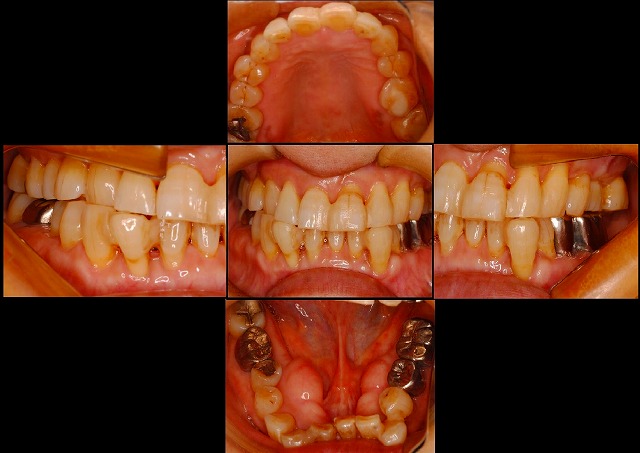

治療開始前はこんな感じで、前歯の下側を真っすぐにしてほしいという希望でした。

奥歯が前に倒れ過ぎていて、そこをかなり後ろにさげながら起こすという方法を取らないといけないので、